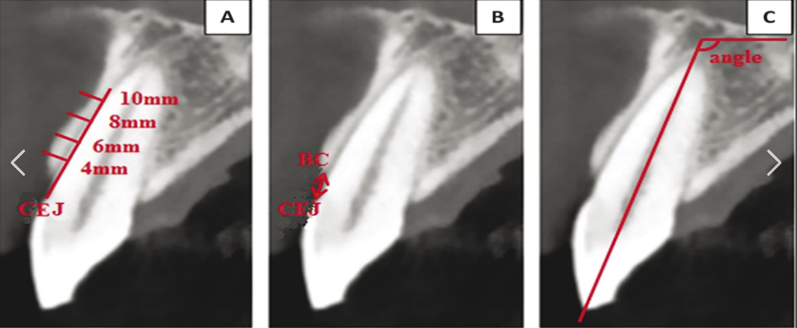

- Mandibular nerve mapping:

- Clear visualization of the inferior alveolar nerve canal

- Maintenance of a minimum 2mm safety distance from the nerve

- Consideration of anatomical variations in nerve position

- Mesiodistal positioning:

- Maintain 3mm minimum distance between implants to preserve interproximal bone

- Keep at least 1.5mm from adjacent natural teeth to protect the periodontal ligament

- Center implants within the available space for optimal prosthetic emergence

- Buccolingual positioning:

- Position implant with sufficient bone (minimum 1mm) on both buccal and lingual aspects

- In the esthetic zone, ensure 2mm buccal bone thickness to prevent recession

- Consider the emergence profile requirements for the final restoration